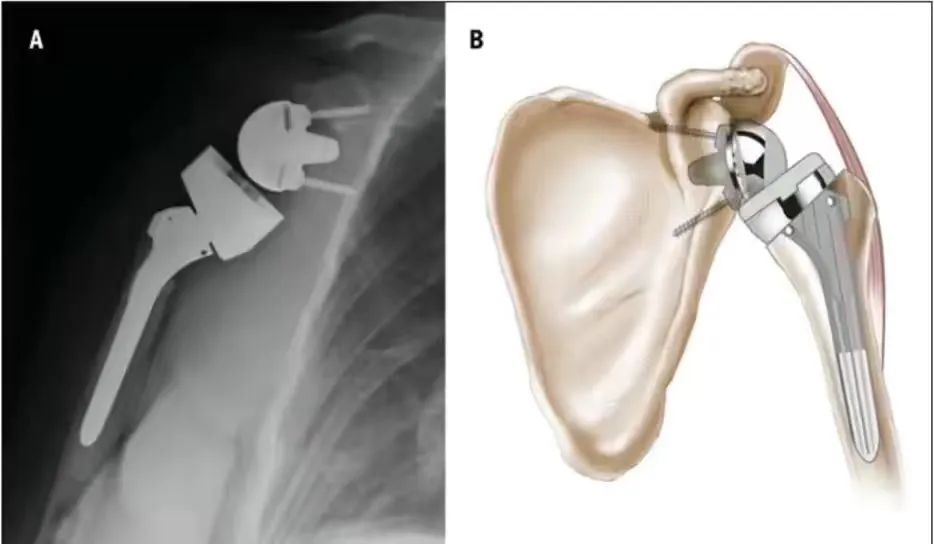

江院长介绍:反式全肩关节置换术( RTSA)是一种对手术技术及配合要求极高的手术。此手术是指肩关节假体的球形关节面放置于肩胛骨关节盂侧,而盂杯放置于肱骨近端的半限制性人工全肩关节,与正常的肱盂关节配对形式正好相反。该术式可以更好地发挥三角肌动力性作用,完成肩关节外展、前屈及内旋活动,从而降低肩关节对肩袖完整性的依赖。另外,该手术需要时间短、并发症少,可有效消除疼痛,快速恢复患者关节功能,提高生活质量。